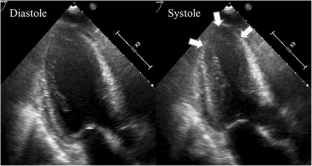

Fig. 4